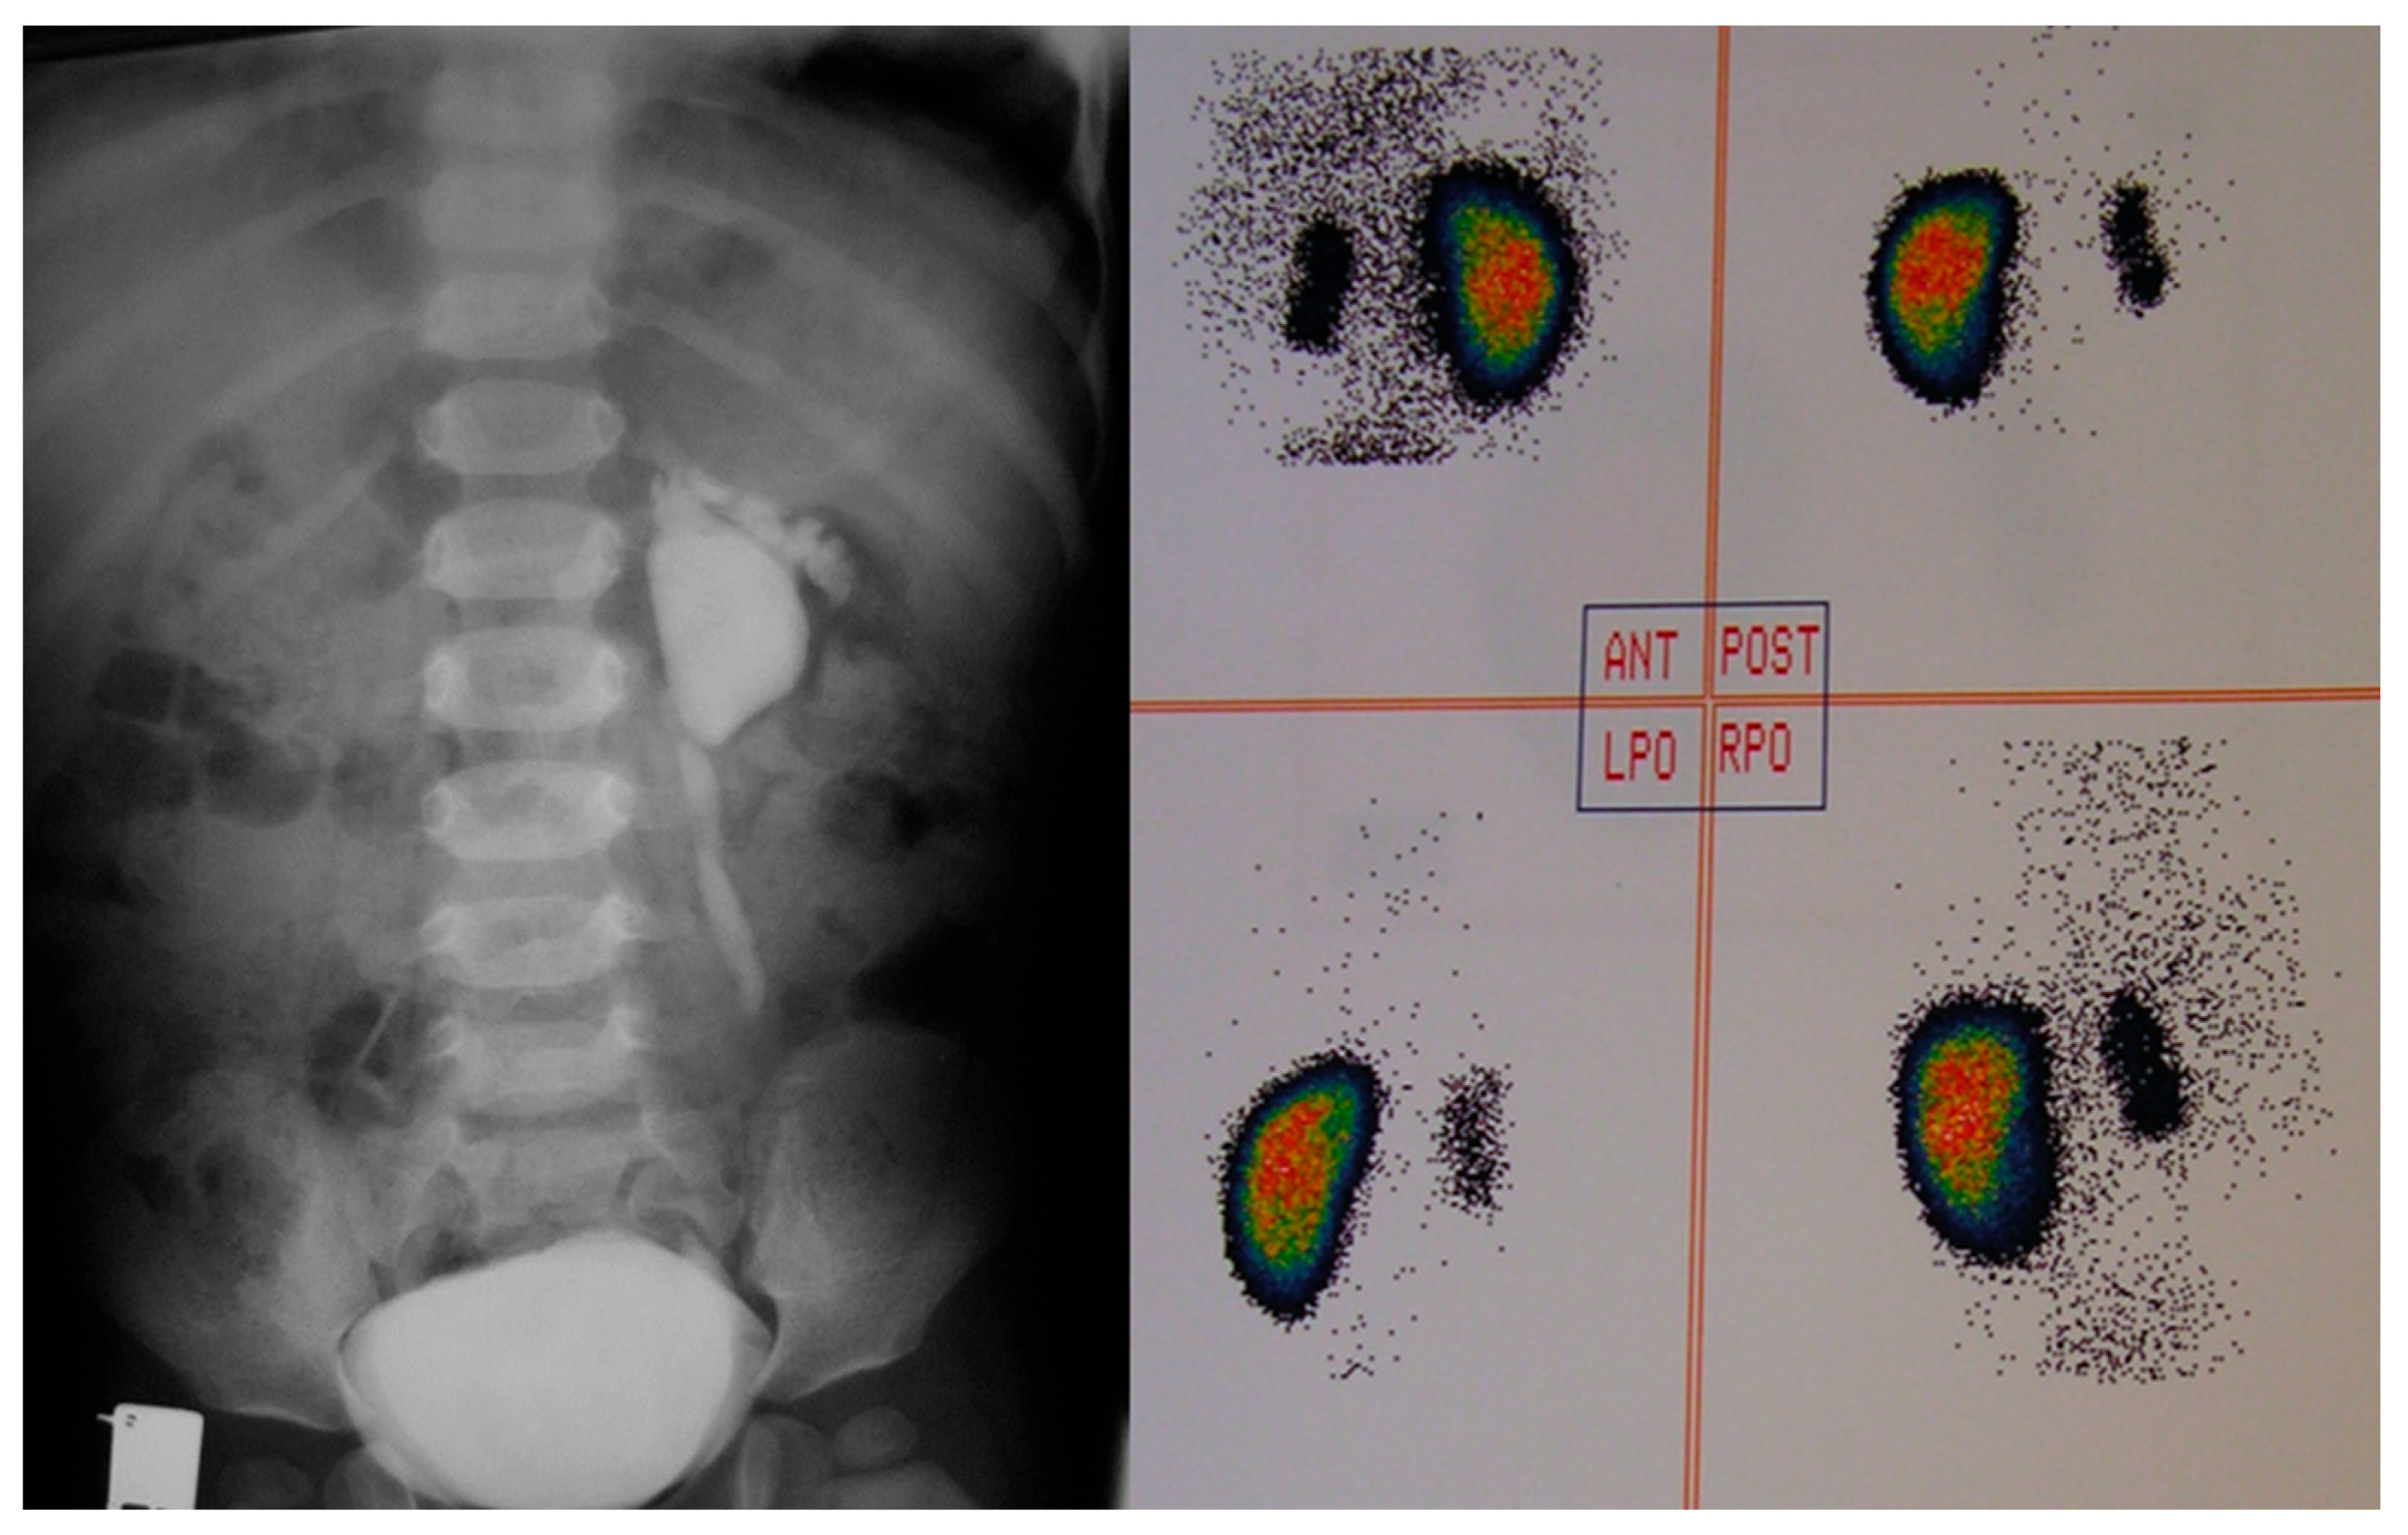

Patients were categorized into two groups based on the presence of a “footprint” sign: Group A (with a “footprint”) and Group B (without a “footprint” sign). The DRF of the affected kidneys in Group A (Figure 2) was compared with the DRF of the refluxing kidneys in patients with unilateral reflux or the kidneys with a higher grade of reflux in patients with bilateral reflux in Group B.

Figure 2.

Different views of Tc99m dimercaptosuccinic acid (Tc99m-DMSA) scan uptake in a refluxing unit with “footprint” shadow. Relative Tc99m-DMSA uptake of the right (footprint) kidney: 8%, the left kidney: 92%. The coloured spectrum in the DMSA scan represents the differential uptake of radiotracer by functioning renal cortical tissue. This spectrum reflects relative perfusion and metabolic activity of kidney function, with colour intensity corresponding to tracer uptake based on count density. Red, orange, yellow: Higher tracer uptake, interpreted as normal or hyper-functioning cortical tissue. Green, blue: Moderate to lower uptake, interpreted as reduced function. Black or absent colour: No uptake, interpreted as non-functioning areas. ANT, anterior; LPO, left posterior oblique; POST, posterior; RPO, right posterior oblique.